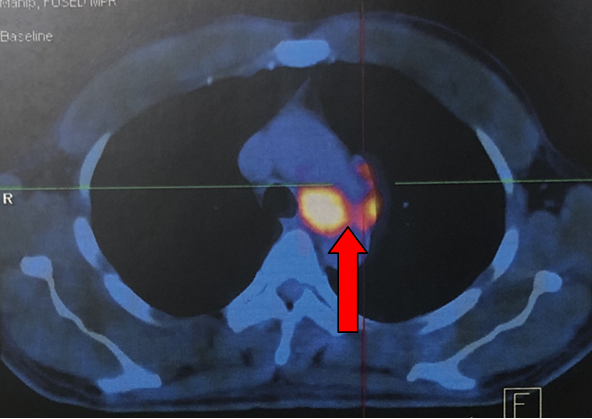

- Hình ảnh chụp cắt lớp vi tính lồng ngực sau điều trị 2 tháng (hình 2a, 2b):

Khối u thùy dưới phổi trái với kích thước 3,0x2,9cm.

Hạch trung thất trái 2,5cm, không thấy hạch rốn phổi.

Không thấy nốt tổn thưởng di căn ở phổi phải.

Hình 2a: Hình ảnh chụp cắt lớp vi tính lồng ngực khối u thùy dưới phổi trái với kích thước 3,0x2,9cm (mũi tên vàng), Không rõ nốt tổn thưởng di căn ở hai phổi.

Hình 2b: Hình ảnh chụp cắt lớp vi tính lồng ngực cho thấy hạch trung thất trái 2,5cm (mũi tên đỏ), không rõ hạch rốn phổi.